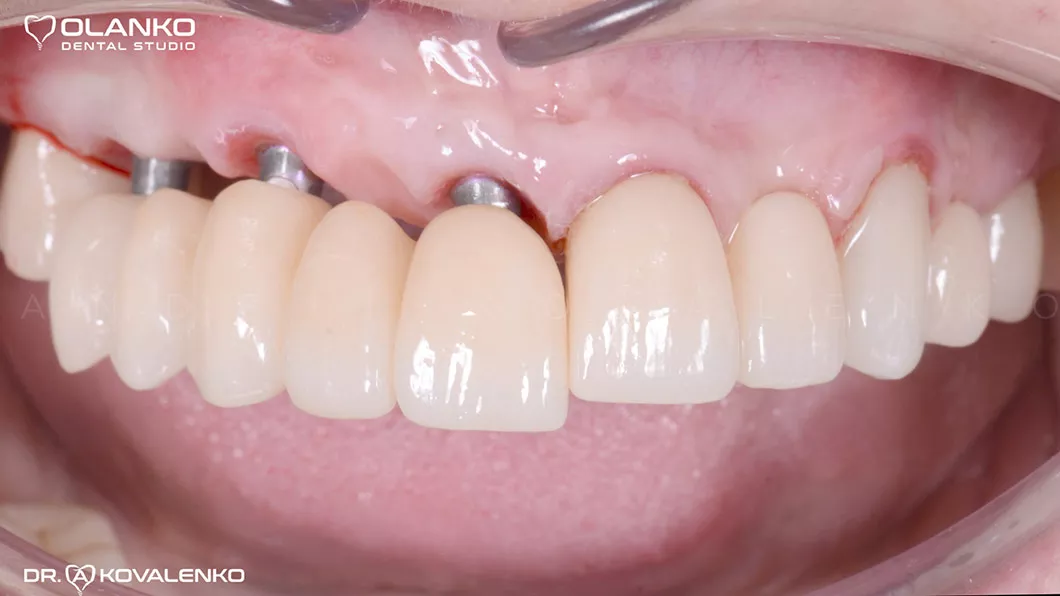

Вид перед установкой керамических коронок на зубах и зубных имплантатах

Процесс установки цельнокерамического мостовидного протеза с опорой на имплантаты

Лечение: снятие старых коронок и мостовидных протезов. Удаление зубов, не подлежащих лечению. Костная пластика и десневая пластика. Установка 3-х зубных имплантатов на верхней челюсти и 2-х имплантатов на нижней челюсти.

Протезирование: цельнокерамическими мостовидными протезами и коронками на зубах, имплантатах.